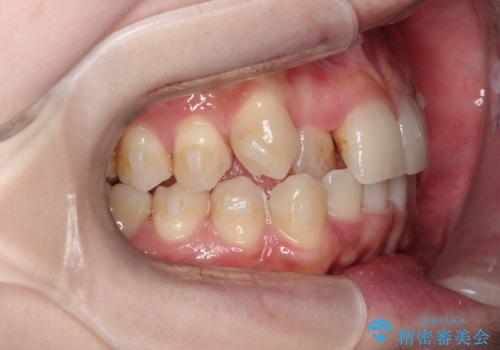

- 八重歯を治したいとのことで来院されました。

右上の犬歯が外側に飛び出して、二番目の歯が内側に入っている状態でした。

上の奥歯を後方に移動させてスペースを確保して、前歯のガタガタを改善する計画としました。

奥歯を後方に移動することで、歯を抜かずに矯正を終えることができました。